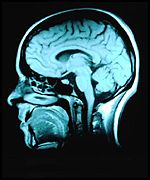

Apesar desse desejo de se ter uma boa mem?ria e das v?rias receitas para se conquistar isso, o fato ? que esse campo ainda n?o ? plenamente conhecido e, ent?o, muitas pesquisas e estudos t?m sido feitos sobre os processos de mem?ria. O processo de memoriza??o ? complexo, envolvendo sofisticadas rea?es qu?micas e circuitos interligados de neur?nios.

A partir desses estudos sabe-se que a mem?ria ? o meio pelo qual uma pessoa recorre ?s suas experi?ncias passadas a fim de usar essas experi?ncias no presente. A mem?ria, de acordo com Crowder (1976 citado por Sternberg 2000), refere-se aos mecanismos din?micos associados ? reten??o e ? recupera??o da informa??o sobre a experi?ncia passada. Os psic?logos cognitivos revelam que nesse processo mnem?nico s?o identificados, segundo Sternberg (2000), tr?s opera?es comuns: codifica??o, armazenamento e recupera??o. Assim, na codifica??o, dados sensoriais s?o transformados numa forma de representa??o mental; j? no armazenamento, a pessoa conserva a informa??o codificada na mem?ria; e na recupera??o o indiv?duo extrai ou usa a informa??o armazenada na mem?ria.